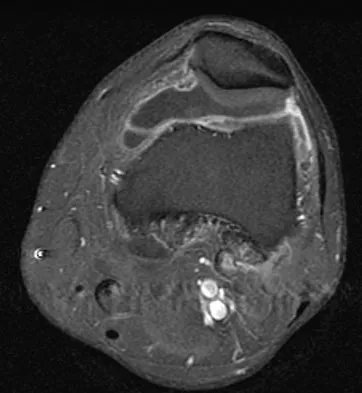

A 28-year-old man reports knee stiffness, swelling, and a constant ache that is worse with activity. Examination reveals an effusion, global tenderness, and warmth to the touch. Flexion is limited to 110 degrees. Figures 48a through 48d show sagittal T1-weighted, sagittal T2-weighted, axial T1-weighted fat-saturated gadolinium, and axial gradient echo MRI scans. Based on these findings, what is the most likely diagnosis?

Explanation